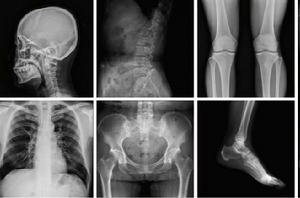

X射線

波長介於紫外線和γ射線間的電磁輻射。由德國物理學家W.K.倫琴於1895年發現,故又稱倫琴射線。是由x光機產生的高能電磁波。波長比γ射線長,射程略近,穿透力不及γ射線。有危險,應禁止(幾毫米鉛板)。